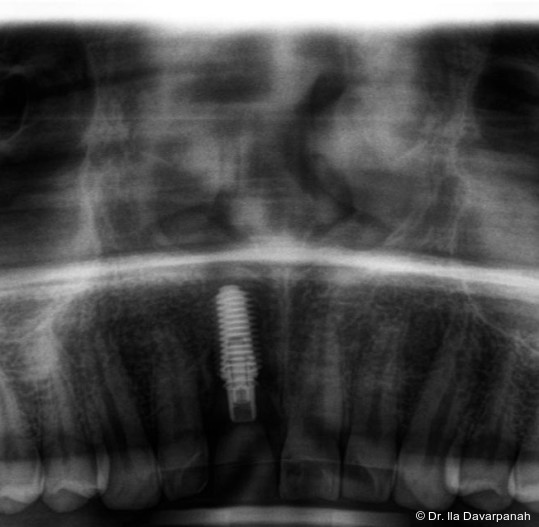

Zur Erreichung einer hohen Primärstabilität wurde ein Implantat mit aggressivem Gewinde bei einem Außendurchmesser von 3,5 mm und einem Kerndurchmesser von ca. 2,8 mm eingesetzt. Ergänzend erfolgte eine unterpräparierte Bohrung. Solche Kombinationen aus Gewindedesign, Implantatgeometrie und Bohrprotokoll sind in der klinischen Praxis etabliert, erfordern jedoch eine sorgfältige Risikoabschätzung hinsichtlich der mechanischen Belastung des Implantatkörpers.

Postoperativ kam es trotz korrekter Implantatpositionierung und regelrechter Sofortversorgung zu einer Fraktur des Implantatkörpers im Bereich der Implantatschulter. Die radiologische Diagnostik mittels Röntgen und DVT zeigte ein Aufplatzen des Implantats im Übergangsbereich zwischen Konusverbindung und Implantatplattform. Das Frakturmuster deutete auf eine strukturelle Überlastung im hoch beanspruchten Schulterbereich hin. Implantatfrakturen stellen insgesamt eine seltene, jedoch für Patient und Behandler belastende Komplikation dar. Sie treten bevorzugt in Regionen mit erhöhten Biege- und Querkräften auf, insbesondere in der Frontzahnregion und bei frühzeitiger funktioneller Belastung.